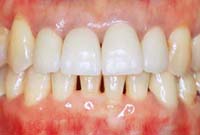

そして、治療終了後20年たったのがこちら!

顎の位置も整い、歯列もそれと調和しているため、歯並びは安定し、歯肉の状態も改善しています。また、患者さんが日々のホームケアをしっかりやってくださっていることも重要です。